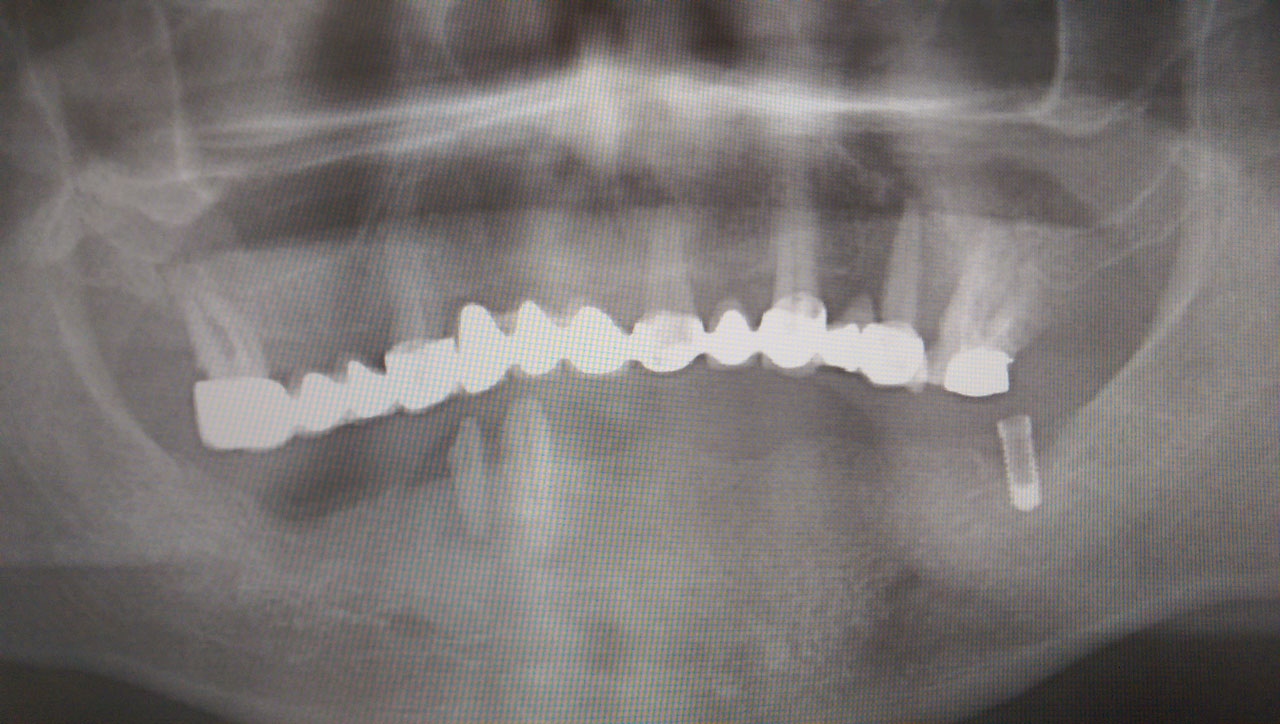

Alsó állcsont teljes rehabilitációja 72 óra alatt

Alsó állcsont teljes rehabilitációja 72 óra alatt, azonnal terhelhető implantátumokkal súlyos paradontitisben szenvedő dohányzó páciens esetében. Az alsó állcsont fogai mind mozogtak az előrehaladott fogágypusztulás miatt.

A fogakat eltávolítottuk, a gyulladt, fertőzött csontot kitakarítottuk, kifertőtlenítettük, majd azonnal implantáltunk.

Svájci, IHDE márkájú, azonnal terhelhető implantátumokat helyzetünk be, és ezekre harmadnapra rögzített, hosszútávú, fémvázas, esztétikus műanyaggal leplezett hidat ragasztottunk be.

Ezt az ideiglenes hidat a sebek gyógyulása miatt használjuk, de tartóssága miatt véglegesként is használható.

A legtöbb esetben, ahogy itt is, 6 hónap múlva porcelán hídra cseréljük, a teljes gyógyulás után.